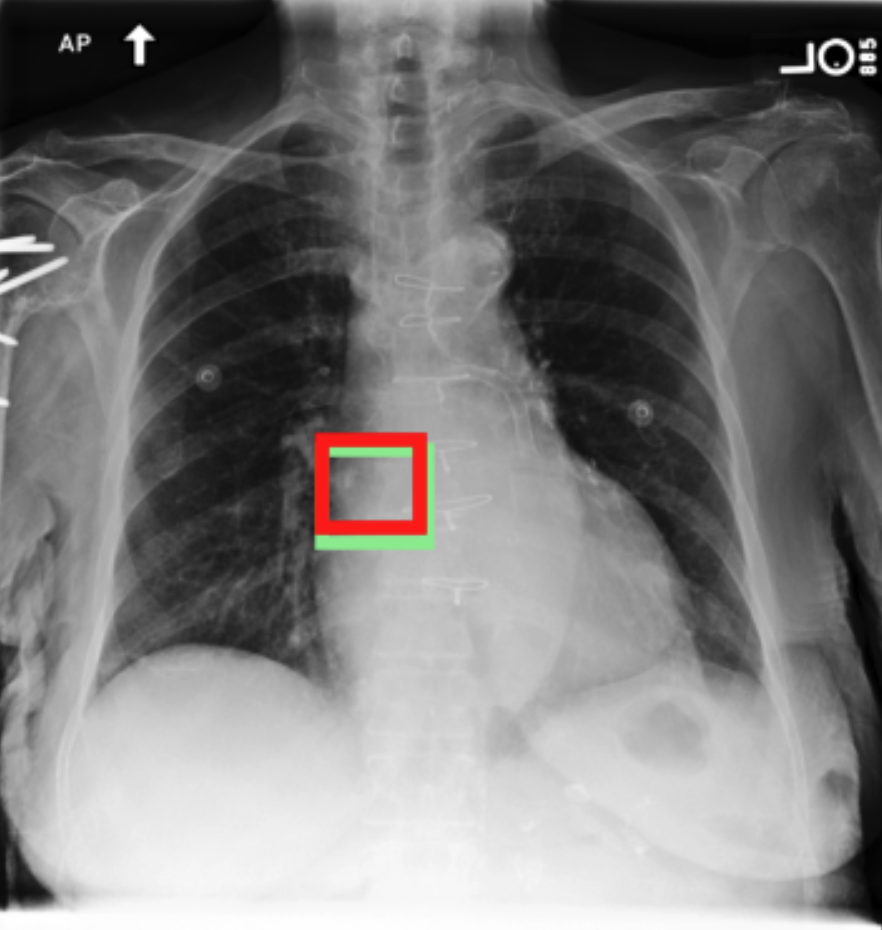

4.3.3 Visual grounding

In this section, we evaluate RadVLM’s visual grounding capabilities, which could help clinicians localize specific regions or pathologies on a CXR. This is particularly useful once a pathology has already been identified – either by a radiologist’s input or through our previously described AI tasks – since it allows one to pinpoint exactly where the abnormality appears on the image.

We report performance metrics for the three main grounding tasks RadVLM was trained on: anatomical grounding using the Chest Imagenome test set, abnormality grounding using the VinDr-CXR test set, and phrase grounding using the MS-CXR test set (Table 1). For each task, we use mean Average Precision (mAP) as our primary evaluation metric.

Our results show that RadVLM performs well at localizing anatomical regions (e.g., “right lung”, “aortic arch”, illustrated in Figure 5a), achieving a mAP of 85.8 %, by far surpassing the other CXR grounding models (Table 4). This advantage is partly explained by including the Chest Imagenome dataset (and thus the anatomical grounding task) in the training set, which CheXagent and MAIRA-2 did not leverage. However, it remains a key feature for any grounding model to possess a fine-grained understanding of CXR anatomy.

For the abnormality grounding task, RadVLM is less consistent (Figure 5b), likely due to higher sparsity of abnormality locations and labels, yet it still achieves best performance (Table 4). For the phrase grounding task, while MAIRA-2 and CheXagent demonstrate great performance, RadVLM surpasses them with a mAP of 81.8% (Table 4), presumably benefiting from the newly released PadChest-GR dataset (Castro et al.,, 2024) used for training.

Overall, these results show that our instruction tuning strategy for visual grounding (covering three essential tasks), combined to a modern VLM backbone, offers a promising avenue to help clinicians localize anatomical and pathological features during a CXR exam. Furthermore, providing fine-grained details within an LLM-generated output may also enhance the ability to answer grounded questions in a multi-turn setting, as we explore next.

b. Abnormality grounding

thickening

fibrosis

enlargement

lung disease

| Anatomical grounding | Abnormality grounding | Phrase grounding | |

| CheXagent | 6.2 | 26.0 | 69.7 |

| MAIRA-2 | 19.8 | 11.3 | 80.1 |

| RadVLM | 85.8 | 34.6 | 81.8 |